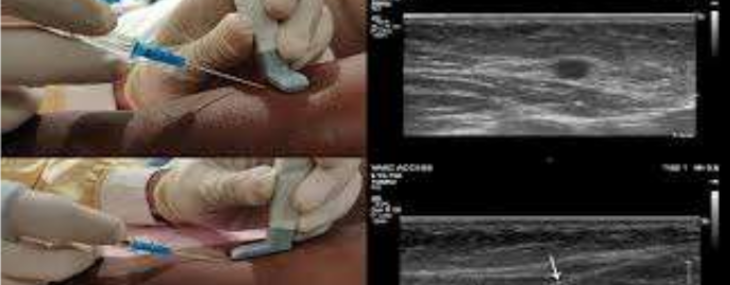

Tecniche di incannulamento vascolare periferico ecoguidato nel neonato, bambino ed adulto: trasversale, longitudinale, obliqua (F. Sacco - Sostituti C. Caroselli, G. Pagano)